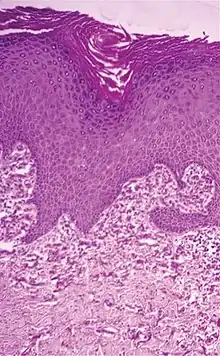

| Elastosis perforans serpiginosa | Degenerated elastic fibers and transepidermal perforating canals (arrow in image points at one of them)[11] |  |